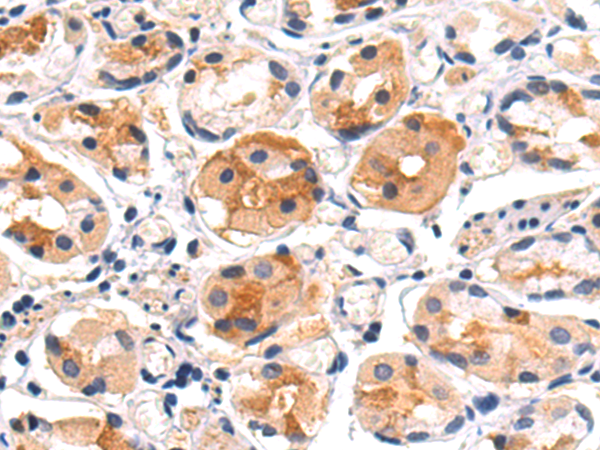

分类: 科研抗体货号: P10813别名: SAG; GP340; SALSA; muclin应用: IHC反应种属: Human, Mouse, Rat